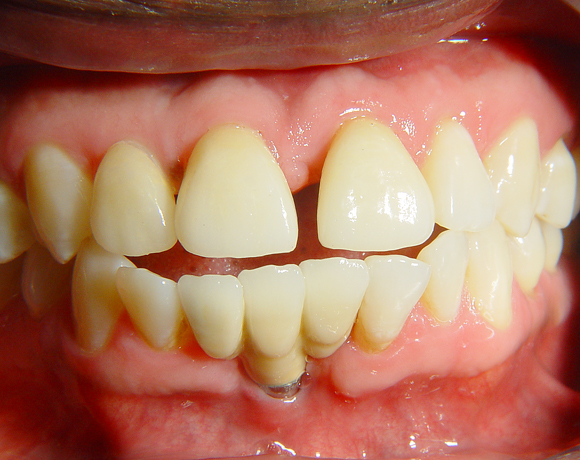

Diese Frontzahnsituation stellte den Behandler vor größere Probleme

Durch Abrasion der Seitenzähne wurden die Frontzähne nach labial verdrängt und lückig. Nach Verlust des Zahnes 41 entstand eine Lücke in der drei Zähne Platz fanden. Auch im Oberkiefer wurden die lateralen Lücken mit Veneers verkleinert.